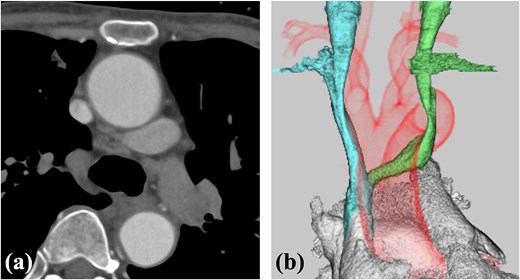

A 78-year-old woman with severe mitral regurgitation (MR), tricuspid regurgitation, and atrial fibrillation was admitted with worsening heart failure. She had hypertension, but no known CHD. She was 138 cm tall, weighing 34.6 kg, with a body mass index of 18.3 kg/m2. Her vital signs were normal. The N-terminal fragment of pro B-type natriuretic peptide was elevated at 2577 pg/mL. Chest radiography revealed cardiac enlargement and bilateral pulmonary edema. Transesophageal echocardiography (TEE) revealed shortening of the anterior and posterior leaflets of the mitral valve, with thickening of the commissure, indicating severe MR (Fig. 1 and Video 1). The tricuspid annulus diameter increased to 29.4 mm. No congenital heart diseases were detected. Contrast-enhanced computed tomography (CT) revealed that the left innominate vein coursed posterior to the ascending aorta, the so-called ALBCV, and joined the superior vena cava (SVC) 3 cm from the right atrium (Fig. 2 and Video 2). Venography of the left upper limb confirmed the ALBCV (Fig. 3 and Video 3). No communication existed between the ALBCV and the coronary sinus.

Contrast-enhanced CT. (a) The ALBCV coursed posterior to the ascending aorta. (b) The ALBCV joined the SVC at a peripheral location ⁓3 cm from the right atrium. No right aortic arch or double aortic arch was observed.